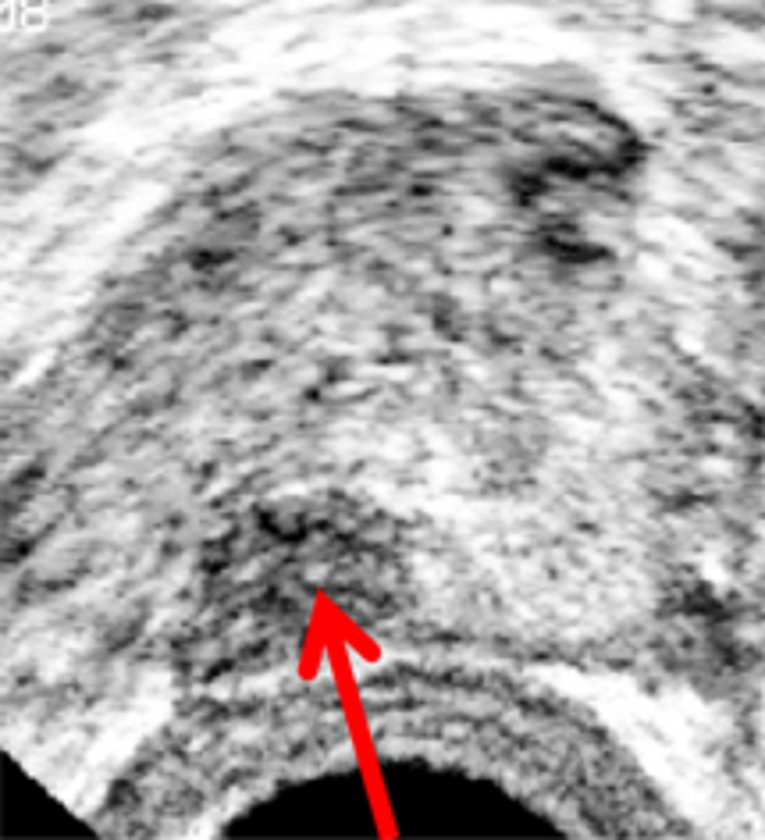

Hierbei wird eine Ultraschallsonde über den Enddarm eingeführt. Über die Ultra-schallsonde kann die Prostata, sowie auffällige bzw. krankhafte Areale dargestellt werden. Diese werden dann gezielt mit der Biopsienadel punktiert und zur feingeweblichen Aufarbeitung in die Pathologie eingesendet.